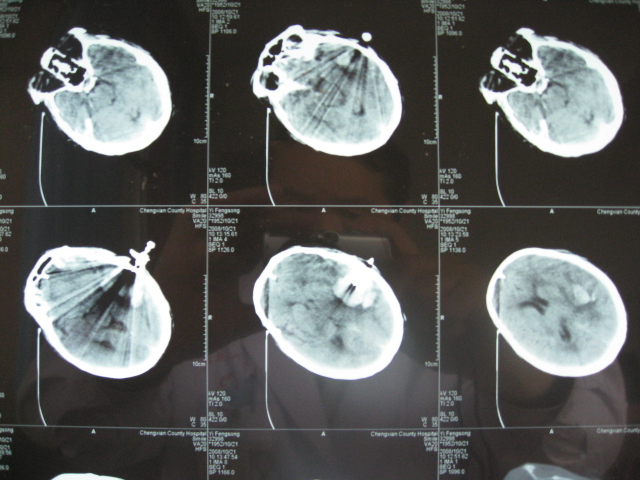

尹** 男 , 56岁,于2008年10月19日11pm以“高血压脑出血”收住院。当时患者昏迷,右侧肢体偏瘫,Bp180/110mmHg,头部CT报告:左侧基底节可见一片状高密度阴影———脑内血肿(量约45ml)。次日8Am行颅内血肿微创清除术,清除血量约30ml,术后继续引流出约10ml淤血。术后第二天患者清醒,第三天患侧肢体恢复自主运动,肌力三级。术后13天能自行站立,术后1月能独立行走。复查CT,颅内淤血完全消失。